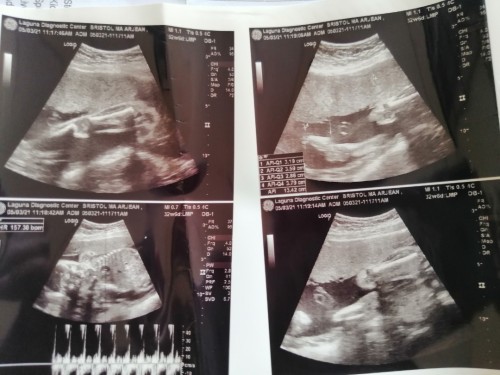

Mga mamshi sino po dito same case ko na kapag nahiga nasaket ang puson hanggang balakang, tapos po kapag nakahiga naman po kapag magturn left/right ako sobrang saket po ng puson ko as in kailangan sobrang dahan dahan. 🥺 kapag naman po nakatayo nangangalay po ang balakang ko tapos kapag nakaupo naman po, yung puson ko at balakang pagtayo galing sa pag kakaupo ansakit. Tapos panay panigas yung tyan ko po. Ano po kaya ibigsabihin non mga mamshi? sana po masagot may same case po ba ko dito? 😭😭😭😭😭😭😭#firstbaby #pleasehelp #1stimemom #pregnancy #advicepls